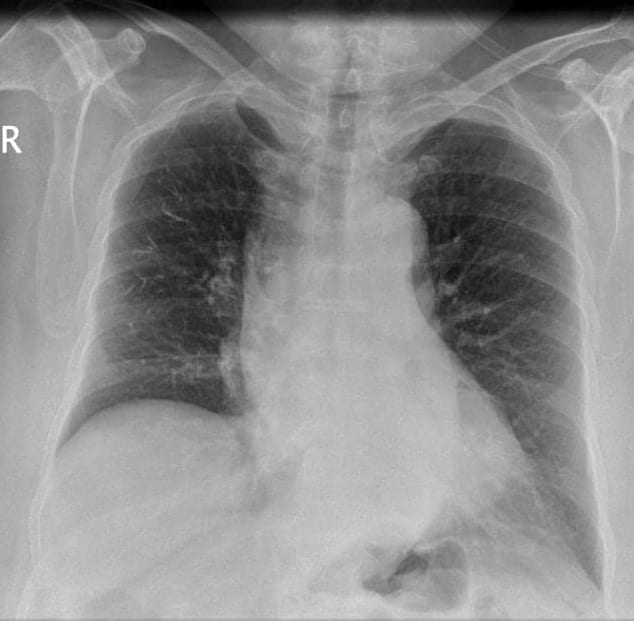

- CXR: Decreased vascular markings , dense tubular branching opacities in the right lung. No signs of consolidation or atelectasis.

Cement embolism secondary to PVP for treatment of osteoporotic vertebral compression fractures mainly based on the CXR and CT findings.